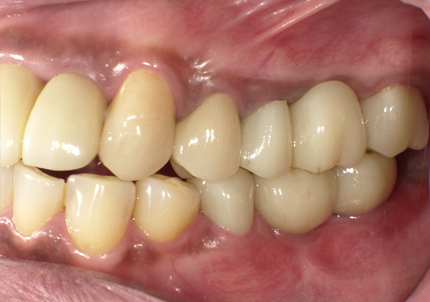

【受傷前口腔内写真】

【受傷後最終補綴物装着】

前歯の受傷前の歯肉の膨らみが、抜歯後にも変わらない状態を維持してインプラント治療されています。患者様、術者も結果がとても良いと満足しています。

13. 最終補綴物装着より4年経過 (2024年10月18日)